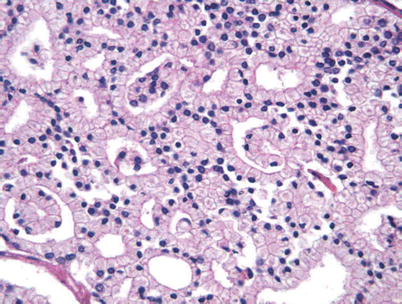

It may grow slowly and it's typically treatable. Histopathology Images Of Adenocarcinoma Acinar Usual Type By Pathpedia Com Pathology E Atlas

Histopathology Images Of Adenocarcinoma Acinar Usual Type By Pathpedia Com Pathology E Atlas from www.pathpedia.com